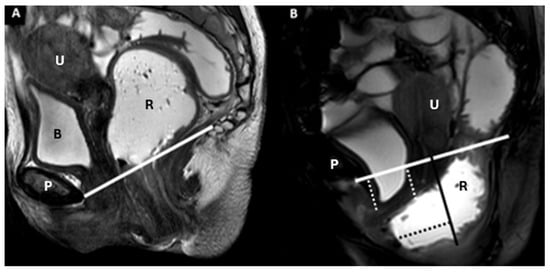

| Pubococcygeal Line (PCL) | Line from the inferior pubic border to the last coccygeal joint | Baseline for measuring organ descent | PCL Compartment Staging Stage 0: Above PCL Stage I: Descent <3 cm below PCL Stage II: Descent 3–6 cm below PCL Stage III: Descent >6 cm below PCL Stage IV: Complete organ prolapse |

| H Line (Hiatal Line) | Distance between the inferior pubic border and the anorectal junction | Assesses puborectal hiatus (anteroposterior dimension during straining) | POP Grade Hiatal Enlargement Normal: <6 cm Mild: 6–8 cm Moderate: 8–10 cm Severe: >10 cm |

| M Line (Muscle Line) | Perpendicular line from the PCL, measuring organ descent | Evaluates posterior pelvic organ descent | Pelvic Floor Descent Normal: <2 cm Mild: 2–4 cm Moderate: 4–6 cm Severe: >6 cm |

| Anterior | Urinary bladder, urethra | Pubocervical fascia (part of endopelvic fascia) | Cystocele (bladder descent) | Bladder neck position relative to PCL | Mild: 1–3 cm, Moderate: 3–6 cm Severe: >6 cm |

| Middle | Vagina, cervix, uterus | Paracolpium, parametrium (endopelvic fascia) | Uterine descent | Uterine fundus position below PCL | Mild: 1–3 cm Moderate: 3–6 cm Severe: >6 cm |

| Vaginal descent | Vaginal fornix position relative to PCL | Mild: 1–3 cm Moderate: 3–6 cm Severe: >6 cm | |||